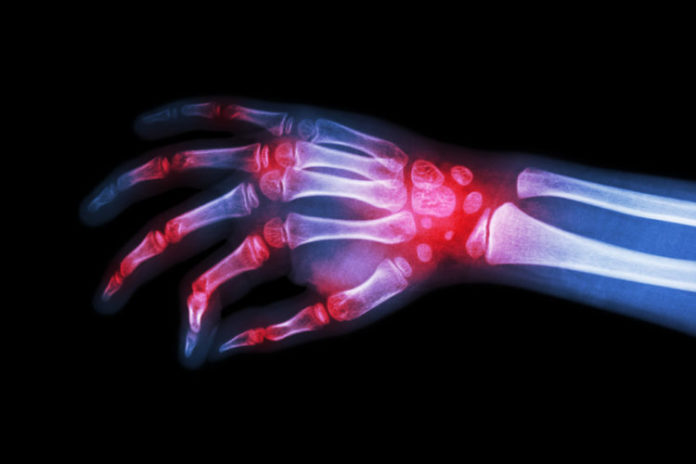

1. Αρθρίτιδα

Στον αρχαίο κόσμο, οι θεραπευτές Αγιουβέρδας πρότειναν την χρήση μιας κρέμας φτιαγμένης από μέλι και κανέλα για την θεραπεία της αρθρίτιδας. Σήμερα, ξέρουμε ότι αυτό λειτουργεί χάρη στην κινναμαλδεΰδη της κανέλας και τα συστατικά του μελιού (κάλιο, κ.α.) τα οποία συνδυάζονται για την θεραπεία της φλεγμονής και των ελλείψεων στην ρίζα της αρθρίτιδας.

Απλά ανακατέψτε δύο κουταλιές της σούπας μέλι με μια κουταλιά κανέλα σε σκόνη. Απλώστε το στο σημείο που πονάτε και κάντε μασάζ στο δέρμα. Μπορείτε ακόμη να ανακατέψετε μέλι και κανέλα σε ένα φλιτζάνι με ζεστό νερό και να το καταναλώνετε συχνά για να ανακουφιστείτε από την αρθρίτιδα.